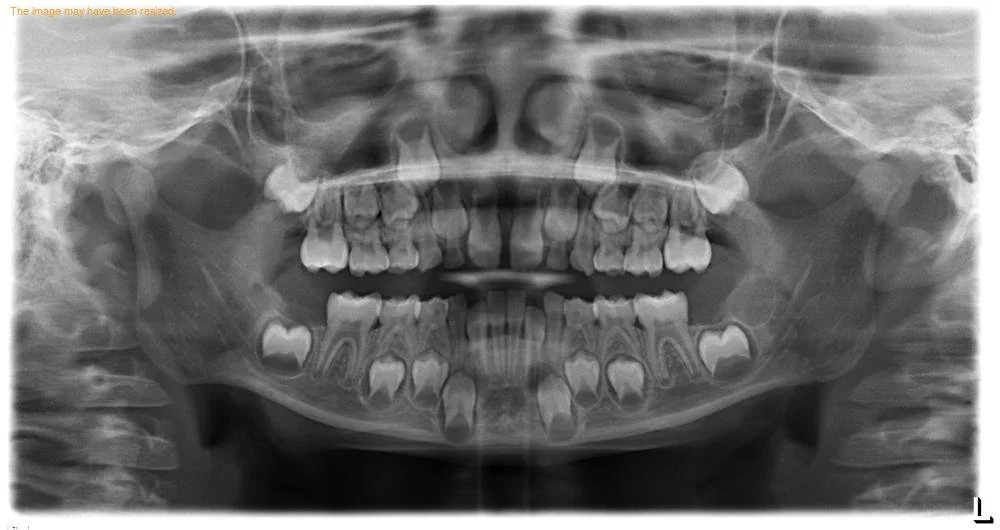

We also take panoramic images at key ages (around 7, 12, and 17) to assess permanent tooth development, jaw growth, wisdom teeth, and any hidden concerns such as cysts or altered tooth position. Early detection allows us to coordinate care with orthodontists and other specialists, minimizing future problems.

Panoramic